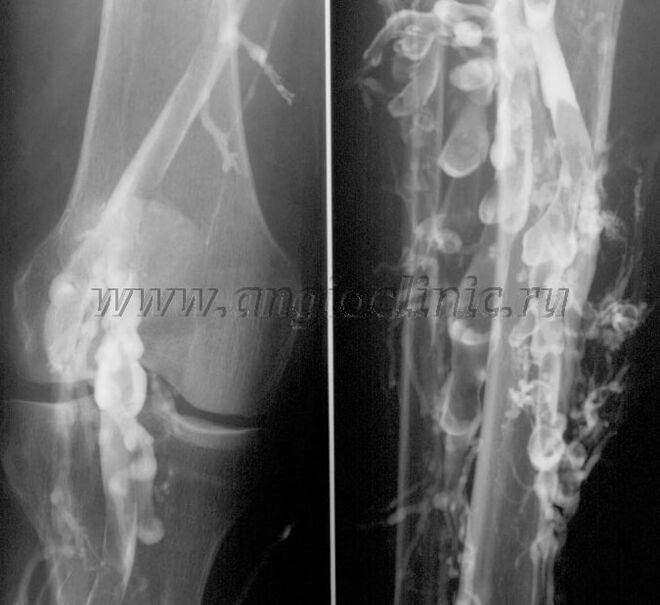

Contrast venography

Usually, ultrasound is sufficient for a complete diagnosis of venous pathology, but in some cases it is necessary to study the relationship between the state of the deep and superficial venous system, especially in case of relapses of varicose veins and secondary varicose veins.

To resolve these problems, a contrast-enhanced X-ray examination is used.The saphenous veins are punctured and contrast is administered.The contrast movement is observed on the monitor of the X-ray machine and all necessary tests and projections are performed.Currently, venography for varicose veins is used very rarely.